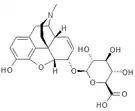

Structures

| Active opiate metabolites | ||||

|---|---|---|---|---|

Codeine-N-oxide Codeine-N-oxide |

Heroin-7,8-oxide Heroin-7,8-oxide |

Morphine-6-glucuronide Morphine-6-glucuronide |

6-Monoacetylmorphine 6-Monoacetylmorphine | |

Morphine-N-oxide Morphine-N-oxide |

Naltrexol Naltrexol |

Norcodeine Norcodeine |

Normorphine Normorphine | |